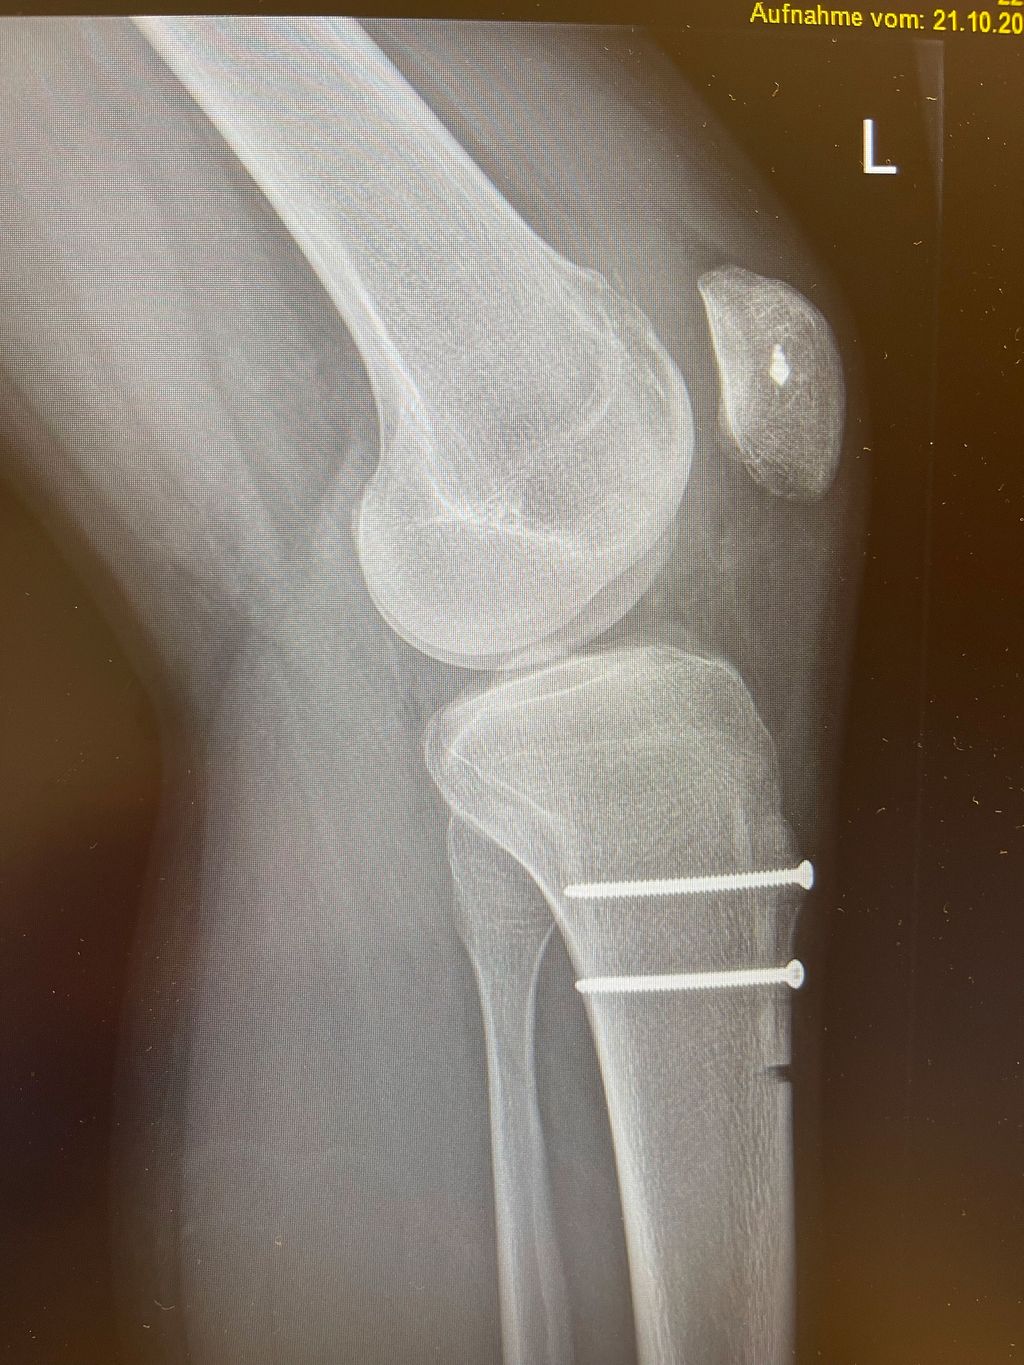

Eine Instabilität bis circa 30° ohne weitere Auffälligkeiten in der radiologischen Untersuchung wird mittels alleiniger MPFL-Rekonstruktion stabil. Ab circa 0–60° Instabilität gibt es zumeist Probleme mit der knöchernen Führung. Dies kann aufgrund eines zu späten Eingleitens der Patella – einer Patella alta – und/oder des Fehlens einer knöchernen Führung (Trochleadysplasie) auftreten. Unserer Meinung nach bedarf es einer Korrektur der Patella alta ab einem Caton-Deschamp-Index >1,2 (Abb.1) und/oder einer LTI (laterale Trochleainklination) von <17° (Abb. 2). Ab 60° ist zusätzlich ein Problem im Bereich des Alignments wahrscheinlich. Bei einer vermehrten Innenrotation des Femurs und der Tibia bei ca. 35° und/oder valgischer Beinachse ab ca. 5° wird eine Korrektur in Erwägung gezogen (Abb.3). Prinzipiell sind wir bei einer Alignmentkorrektur eher zurückhaltend (von manchen Autoren wird bereits eine Korrektur ab 20° Innenrotation empfohlen).5 Ein vermehrter TTPCL-Abstand (lateraler Kraftvektor der Patella) ab circa 24mm kann die Luxation ebenfalls begünstigen und bei einer Patella alta mitkorrigiert werden. Sollte eine knöcherne Stabilisierung notwendig sein, ist bei der Trochleaplastik eine arthroskopische oder offene Technik möglich.

Bei der Patella alta wird der Ansatz knöchern etwas nach distal versetzt. Die Schnittführung ist lateral parallel zur Tuberositas, die Osteotomie erfolgt tangential unter Schonung der Patellasehne. Als Führung können 2 Kirschnerdrähte parallel entlang der Schnittführung eingebracht werden. Vor der Operation wird als Anhaltspunkt die gewünschte Distalisierung errechnet. Es empfiehlt sich jedoch, intraoperativ den Patellastand mittels Bildwandler zu kontrollieren (Ziel ist ein Caton-Deschamp-Index unter 1). Die endgültige Fixierung erfolgt mit zwei 3,5-mm-Schrauben (Abb. 9).8